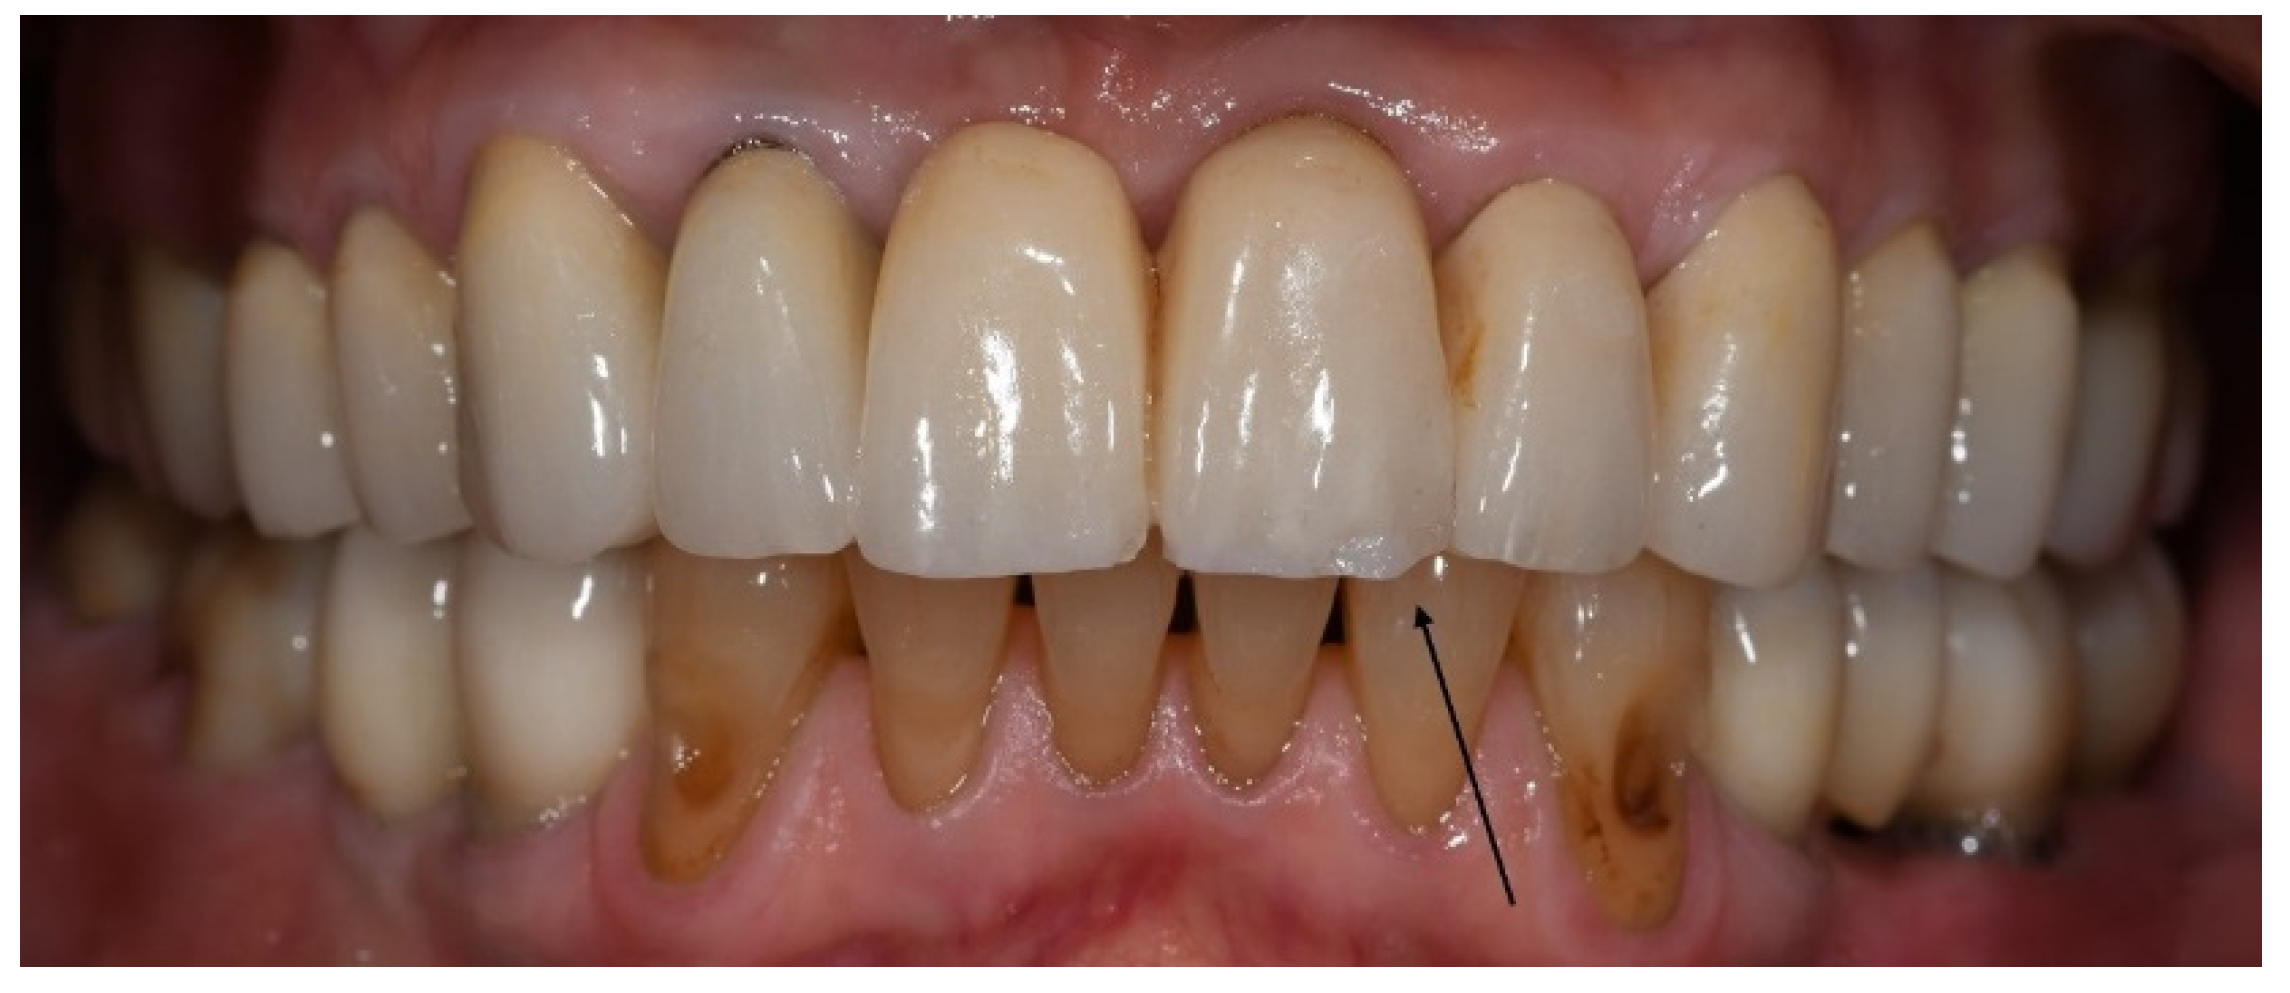

The CDA ratings were divided into those of the bruxer (Figure 3) and the non-bruxer (Figure 4) groups. The bruxer group had 96.7% excellent and 3.3% satisfactory surfaces (due to porcelain chipping and zirconia fracture); 35% excellent color; 87.6% excellent shape (due to three irreparable fractured teeth [0.9%] and five reparable open proximal contacts [1.5%] with another 10%, including the six open proximal contacts without food impaction, were evaluated as having a satisfactory shape); 45% marginal integrity rated as satisfactory (due to over contouring or open margins that led to two cases of secondary caries). The non-bruxer group comprised 98.4% excellent and 1.6% satisfactory surfaces (due to porcelain chipping and zirconia fracture); 45% excellent color; 90.2% excellent shape (due to seven reparable open proximal contacts [2.3%] with another 7.5%, including the six open proximal contacts, without food impaction, evaluated as having a satisfactory shape); and 40% marginal integrity rated as satisfactory (due to over contouring or open margins that led to three cases of secondary caries). Overall, 97.6% and 97.7% of restorations in the bruxer and the non-bruxer groups, respectively, were evaluated as satisfactory and not in need of repair or remake.

Figure 3. CDA ratings for the bruxer group.